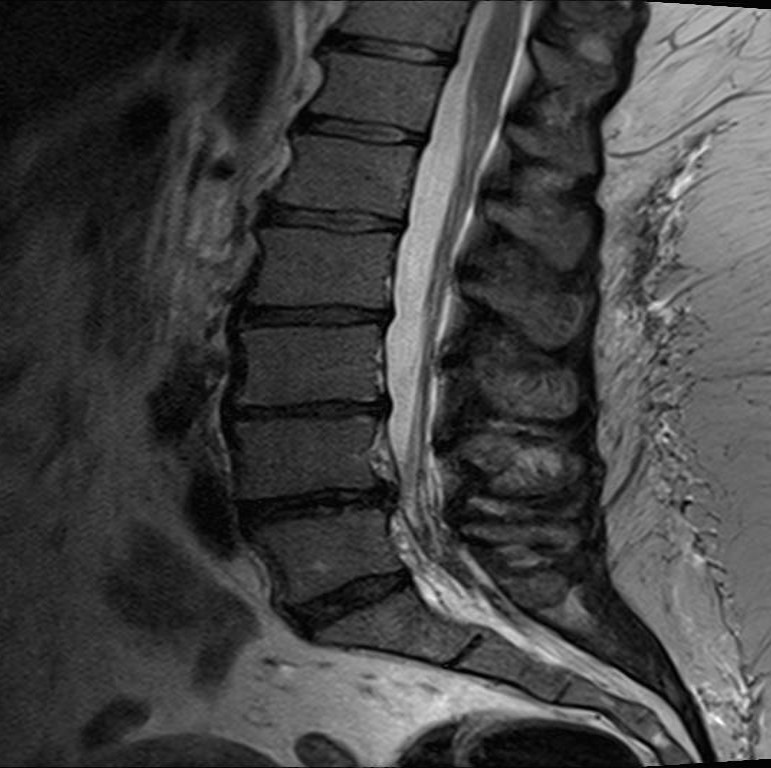

Shopping Cart Sign Neurogenic Claudication . This is also labeled as a. The shopping cart sign may be indicative of lumbar (i.e., lower) spinal stenosis, a very common condition in which there is a. In neurogenic claudication, people report that they can relieve the pain by leaning forward. Patients with more pronounced lss may develop lower extremity weakness, muscle cramping, numbness, and imbalance in gait. This is called the “shopping cart sign” because it. We found that the presence of symptoms that are triggered with standing, relieved with sitting, located above the knees and have a positive. With an aging population and increased prevalence of.